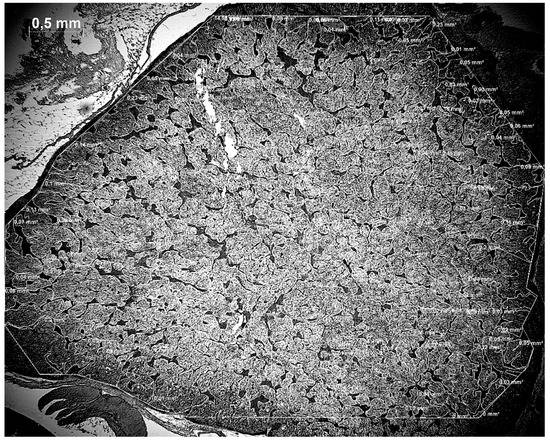

2.3. Microscopical Analysis

3.2. Total Area of Cells in Adrenal Gland and Adrenal–Interrenal Ratio